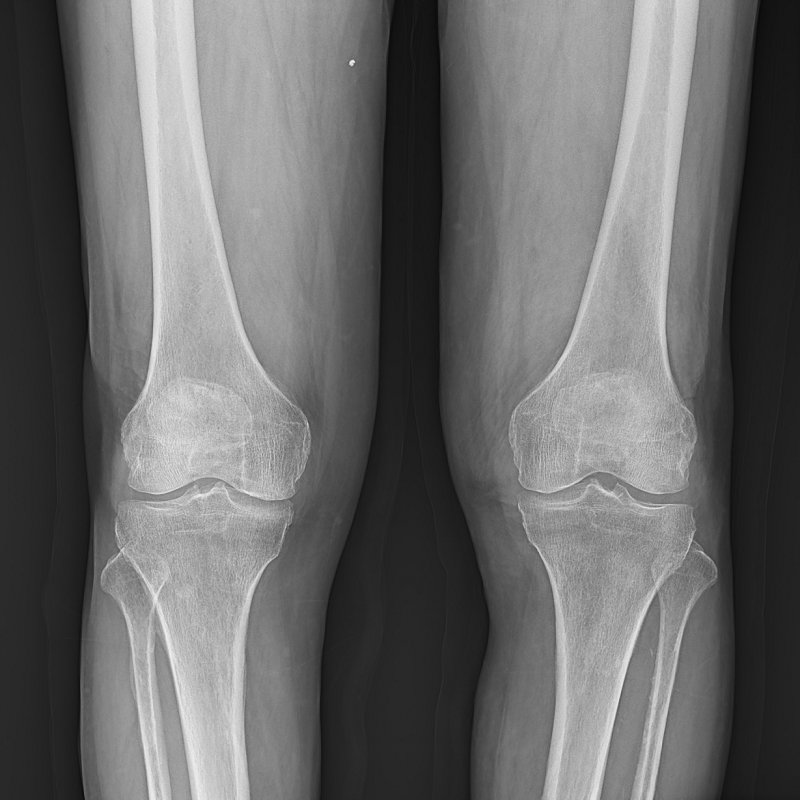

● 低位攝影

球管及胸片架可大范圍縱向移動(dòng),平板探測(cè)器中心最低離地35cm,輕松滿足膝關(guān)節(jié)、踝關(guān)節(jié)等低位攝影的要求。